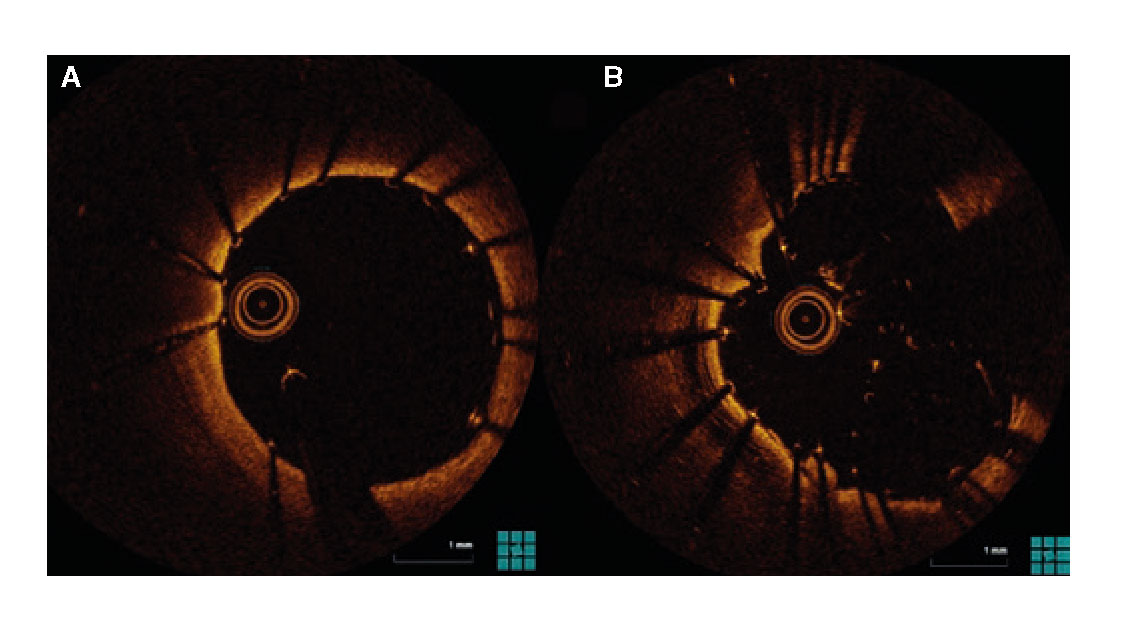

El procedimiento se efectuó bajo anestesia general, mediante abordaje femoral bilateral. Se colocaron 2 catéteres guía Extra Back Up (EBU) de 3,5 mm, de 6 y 7 Fr, en el tronco común izquierdo (técnica ping-pong). Se realizó predilatación secuencial de los ostia coronarios de la descendente anterior y las ramas intermedias mediante un balón de corte de 2,0 mm (vídeo 1 del material adicional) y se implantaron simultáneamente 3 stents farmacoactivos en la descendente anterior (stent liberador de sirolimus, de 2,25 × 15 mm), la primera rama intermedia (stent liberador de zotarolimus, de 2,25 × 18 mm) y la segunda rama intermedia (stent liberador de sirolimus, de 2,25 × 18 mm), por este orden; posteriormente se realizó un inflado simultáneo (figura 2). Por disección retrógrada se implantó un cuarto stent farmacoactivo (stent liberador de zotarolimus, de 4 × 8 mm) en el tronco común izquierdo (figura 3 y vídeo 2 del material adicional), con buen resultado por tomografía de coherencia óptica (figura 4A, B). Inmediatamente después de la intervención coronaria percutánea (ICP) se implantó una válvula aórtica expandible con balón de 23 mm (figura 5 y vídeo 3 del material adicional), también con buen resultado (figura 6 y vídeo 4 del material adicional).

Figura 4. Tomografía de coherencia óptica tras la intervención coronaria percutánea. Buena expansión y aposición del stent en el tronco común izquierdo (A), así como de los stents en la trifurcación con una luz adecuada (B).